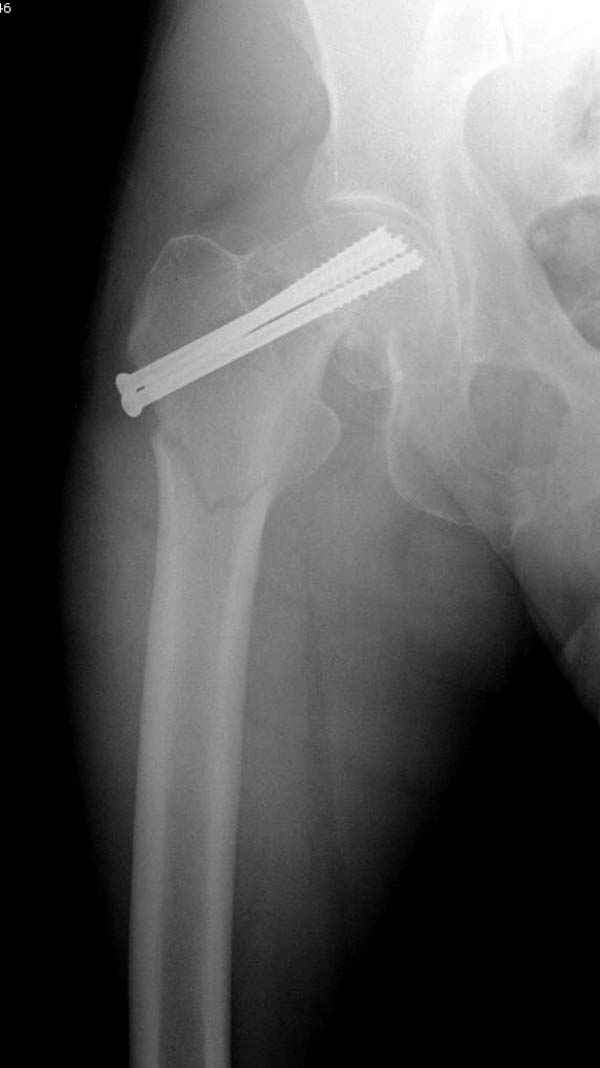

На второй день после выписки упал дома. Снимки приложены. Коллеги рекомендуют удаление шурупа и вытяжение. Что делать?

"Решайте проблемы по мере поступления. На первом этапе решение одно, и на мой взгляд верное. Ситуация изменилась кардинально - другое решение. Я бы избрал ресинтез, убрав винты заменил на Гамму. Что с ним будет послезавтра? - Будем решать послезавтра. Такая наша доля."

Правильно, ситуация изменилась, как говорят у нас теперь "different animal", надо решать проблему подвертельного перелома. При наличии различных вариантов фиксаторов, включая Страйкер Гамма 3, мы выбрали DePuy Antegrade Trachanteric Nail из-за многовариантности проксимальной фиксации и двойного изгиба. Вводится через вертел под 8 градусным углом, и есть достаточный передний диафизарный изгиб, предупреждающий пенетрацию дистального переднего кортекса.

Но ведь и головка бедра сползла в варус - отчего ограничились только фиксацией подвертельного перелома, а не убрали винты и не сделали репозицию шейки?